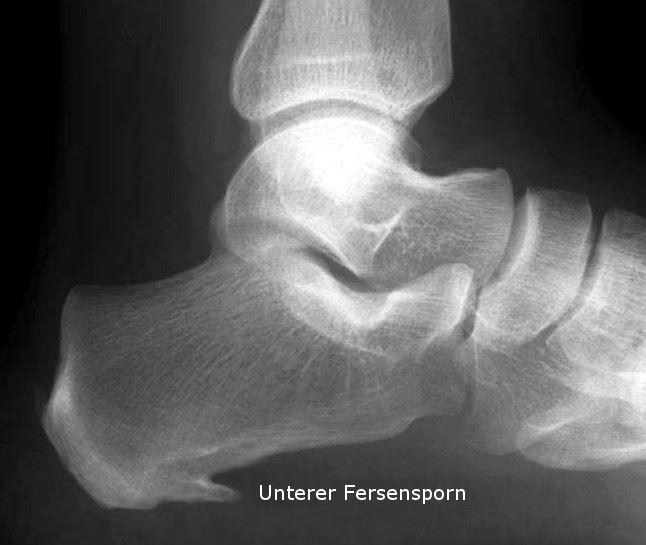

Röntgenaufnahme eines Fersenspornes

Der Fersensporn (Kalkaneussporn) ist eine knöcherne Veränderung am Fersenbein in Form eines dornartigen Gebildes. Dabei wird in der Regel zwischen einem unteren und einem oberen Fersensporn unterschieden.

Beim unteren Fersensporn handelt es sich um einen dornartigen Knochenauswuchs am Fersenbein auf Grund einer Verkalkung des fächerförmigen Bandapparates (Plantarfaszie) an der Fusssohle. Der Sporn ist meist nur wenige Millimeter lang und ist manchmal von einer Entzündung der Plantarsehne (Plantarsehnenentzündung / Plantarfasziitis) an der Fusssohle begleitet. Weniger häufig ist der hintere oder obere Fersensporn anzutreffen. Dabei handelt es sich um eine knöcherne Ausziehung des Fersenbeins am Ansatz der Achillessehne.